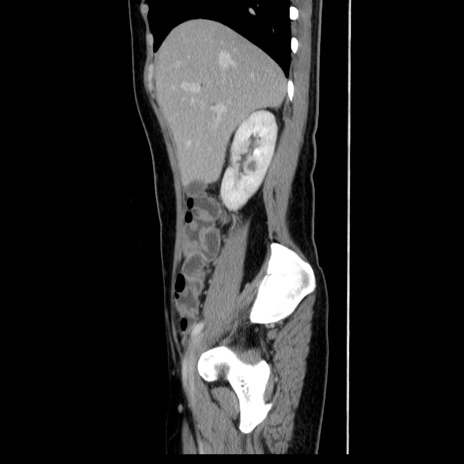

症例39(矢状断像)

【症例】40歳代女性

【主訴】上下腹部痛

【現病歴】2日目から下腹部痛あり。夜間は痛みで眠れなかった。昨日より上腹部痛と下痢が出現。臥位で痛みは軽快したため、休んでいた。本日になって臥位でも立位でも痛みが強くなってきたため救急要請。

【既往歴】子宮内膜症

【身体所見】部:平坦・軟、左上下腹部に圧痛あり、反跳痛あり。

【データ】WBC 21800、CRP 26.78

CT